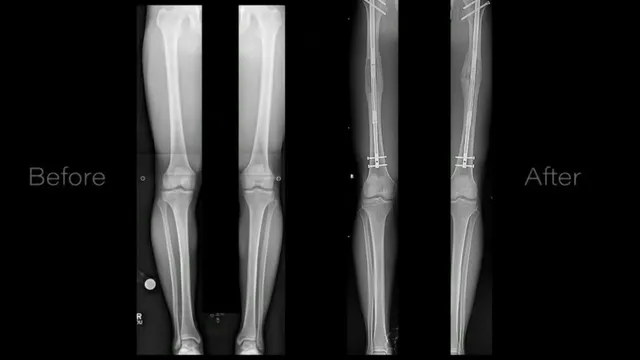

- Asger Walmsley, a seven-year-old with cerebral palsy, successfully trialed a bionic exoskeleton at home.

- The Agilik orthosis costs £72,000, presenting an affordability challenge for many families.

- The trial's success indicates potential for wider access to similar technologies in the future.